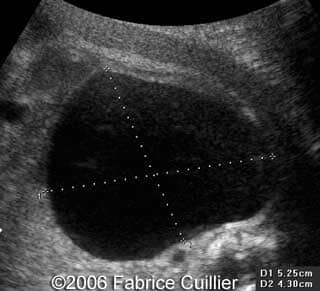

• an abnormal polycystic left kidney (34 X 17 mm) with an abnormal corticomedullar differentiation. This kidney was on the lumbar fossa.

At 24 and 26 weeks, the left kidney lesion had increased. At 34 and 37 weeks, the anomalies were the same. The baby was delivered vaginally (male, 3000 g). At day five, the kidney abnormalities were confirmed. Nevertheless the creatinine level was normal. One month later, a scan revealed a normal right kidney (50 mm) and a left kidney with cysts. The creatinine level was in the normal range. The child was operated (left nephrectomy). The diagnosis of multicystic kidney disease was confirmed.

Note the large cyst